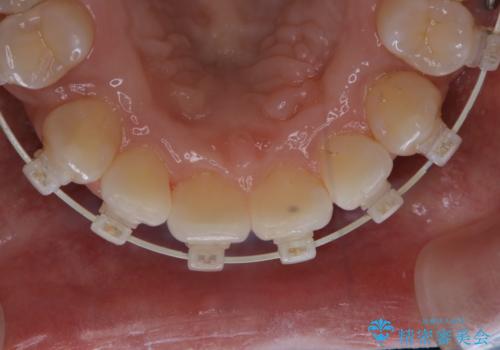

ワイヤー矯正中のPMTC

- ワイヤー矯正中に装置の周りの着色が気になるとのことで来院されました。PMTC30分コースを行いました。

ワイヤー矯正中も、歯の表面に着色(ステイン)が付着することがあります。着色(ステイン)が付着したままだと審美的な問題以外にも、虫歯を発見しずらいことや、細菌が繫殖しやすくなることがあります。クリーニングを行うことで、虫歯や歯周病予防に効果的だったり、もちろん見た目も審美的です。クリーニング後には、汚れが取り除かれ、お口の中がスッキリ・爽快感で気持ちがよくなります。矯正中も定期的にPMTCを行うことが大切です。